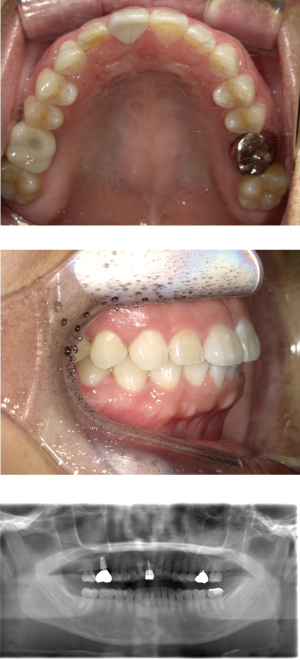

40代 女性 インプラント治療

| 年代・性別 | 40代・女性 |

| 主訴 | 入れ歯を使用した事があるが、違和感が強かったので、見た目も噛み心地も良いインプラントにしたい。 |

| 部位 | 右上7 |

| 治療期間 | 約7ヶ月 |

| 費用 | ¥357,500(税込) |